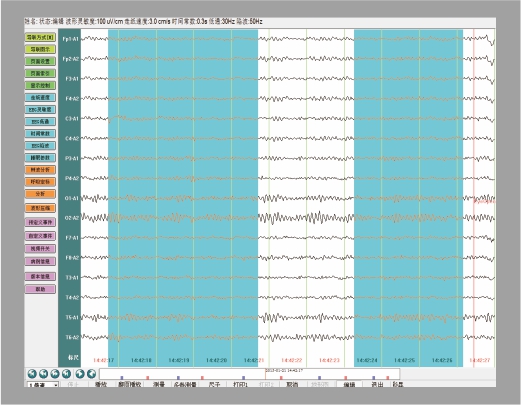

用户便捷操作

导联编辑                                                                               数据库管理

支持单极、双极、自定义任意导联模式的编辑,满足医生不同的检查方式;             病例数据库分类管理,导入、导出数据,方便病例存档、备份;

阻抗测试                                                                                病例编辑

具有头皮阻抗测试功能,通过观察软件指示灯,直观判断电极是否佩戴合适;           支持病例数据剪辑功能,便于医生保存典型波形及教学备案;

多样化测量\

事件标记

具有快捷测量、局部波形放大测量、波形卡尺测量等多种测量功能,满足不同的数据测量需求采集病例时支持睁闭眼、深呼吸、闪光、声刺激等多种事件诱发实验。